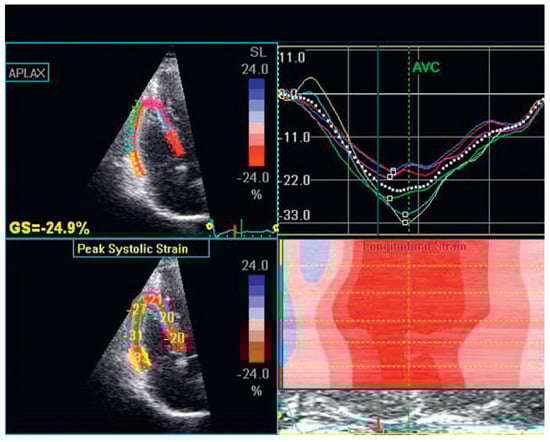

Speckle tracking and three-dimensional echocardiography

- Tong, C.; Li, C.; Song, J.; Liu, H.; Deng, Y. Assessment of right ventricular free wall longitudinal myocardial deformation using specle tracking imaging in normal subjects. J Huazhong Univ Sci Technol. 2008, 28, 194–196. [Google Scholar] [CrossRef] [PubMed]

- Meris, A.; Faletra, F.; Conca, C.; Klersy, C.; Regoli, F.; Klimusina, J.; et al. Timing and magnitude of regional right ventricular function: a speckle tracking-derived strain study of normal subjects and patients with right ventricular dysfunction. J Am Soc Echocardiogr. 2010, 23, 823–831. [Google Scholar] [CrossRef]

- Reali, M.; Rajagopalan, N.; Lopez-Candales, A.; Cordero, K.E.; Suffoletto, M.; Shroff, S.G.; et al. Regional right ventricular myocardial strain by echocardiographic speckle tracking distinguishes clinical and hemodynamic RV dysfunction in pulmonary hypertension. J Cardiac Failure. 2008, 14, 17. [Google Scholar] [CrossRef]

- Pirat, B.; Mcculloch, M.L.; Zoghbli, W.A. Evaluation of global and regional right ventricular systolic function in patients with pulmonary hypertension using a novel speckle tracking method. Am J Cardiol. 2006, 98, 699–704. [Google Scholar] [CrossRef]